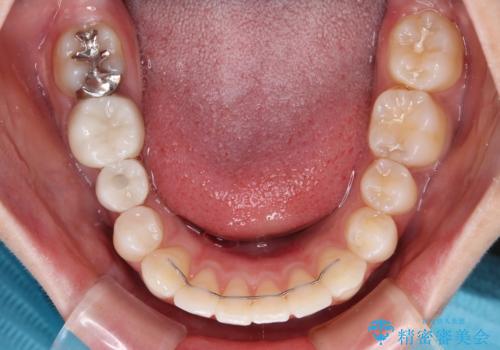

上顎歯列全体を後方移動させたことで唇に当たる感覚は改善され、更には上下の正中位置も合わせることができました。